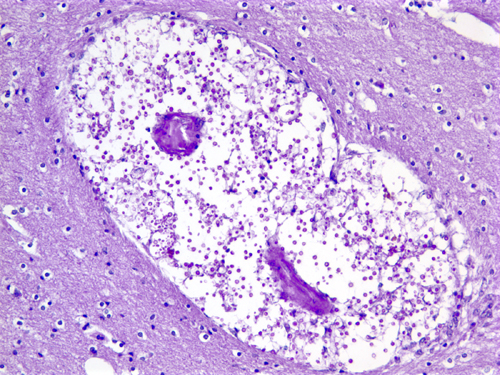

The protozoon Toxoplasma gondii infects approximately one-third of the world’s population. The organism reproduces sexually in the intestinal tract of cats and forms oocysts that are excreted in cats’ feces. Protozoa released form oocysts ingested by animals and humans invade the brain, eye, heart, skeletal muscle, and other organs, where they form tissue cysts. Humans and animals are infected from oocysts in cat feces and from poorly cooked meat containing tissue cysts. Parasites released from oocysts and tissue cysts reside in cell vacuoles and are protected from host defenses. Most primary infections are asymptomatic or cause a self-limited granulomatous lymphadenitis. Latent infections are also silent. If the primary infection occurs during pregnancy, toxoplasma may cross the placenta and cause a devastating necrotizing encephalitis and chorioretinitis in the fetus. The end result of congenital toxoplasmosis is severe brain damage, microcephaly, cerebral calcifications, and blindness. Reactivation of latent toxoplamosis in immunosuppressed individuals, such as patients with HIV/AIDS, causes toxoplasma encephalitis, characterized by necrosis and mononuclear cell infiltrates. The lesions contain single organisms and cysts, which can be identified histologically or by immunohistochemistry. About 25% of patients dying from AIDS have toxoplasma encephalitis.